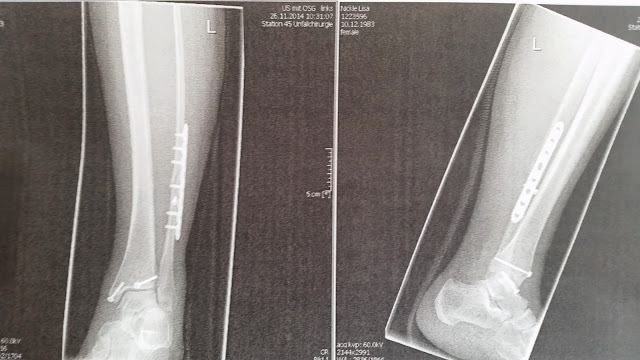

Anyway, I ended up with a giant plate in my leg and a bunch of screws. Its pretty intense. I became THAT person today and posted a picture of my *insert weird thing here*. I think it deserved a shout out.